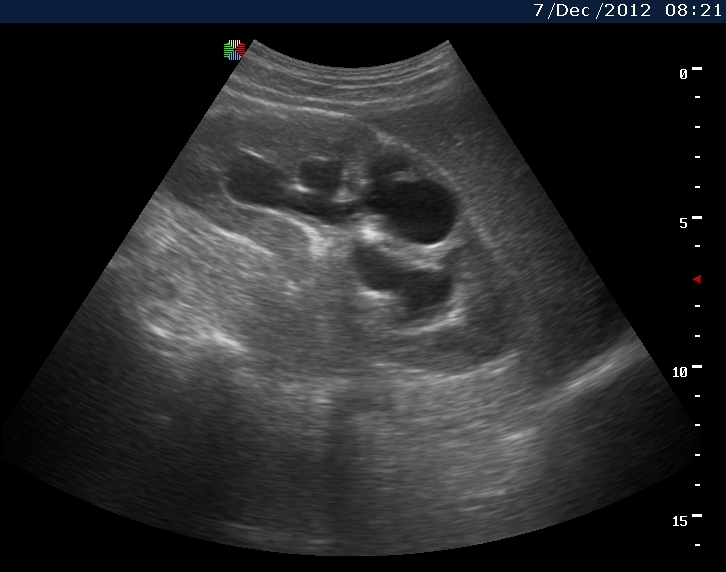

Пациент с подтвержденным туберкулезом почки

Вот как выглядит почка при первом осмотре и в феврале

3февраль.jpg

Видим длительно существующий гидронефроз вследствие процесса в области лоханочно-мочеточникового сегмента (видео 1), с утолщением стенок ЧЛС и истончением паренхимы почки - наиболее частая причина у взрослых - туберкулез.